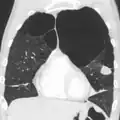

Caso grave de enfisema bolhoso

TAC axial do pulmão de uma pessoa em estado terminal de enfisema bolhoso.

Enfisema muito grave com cancro do pulmão à esquerda